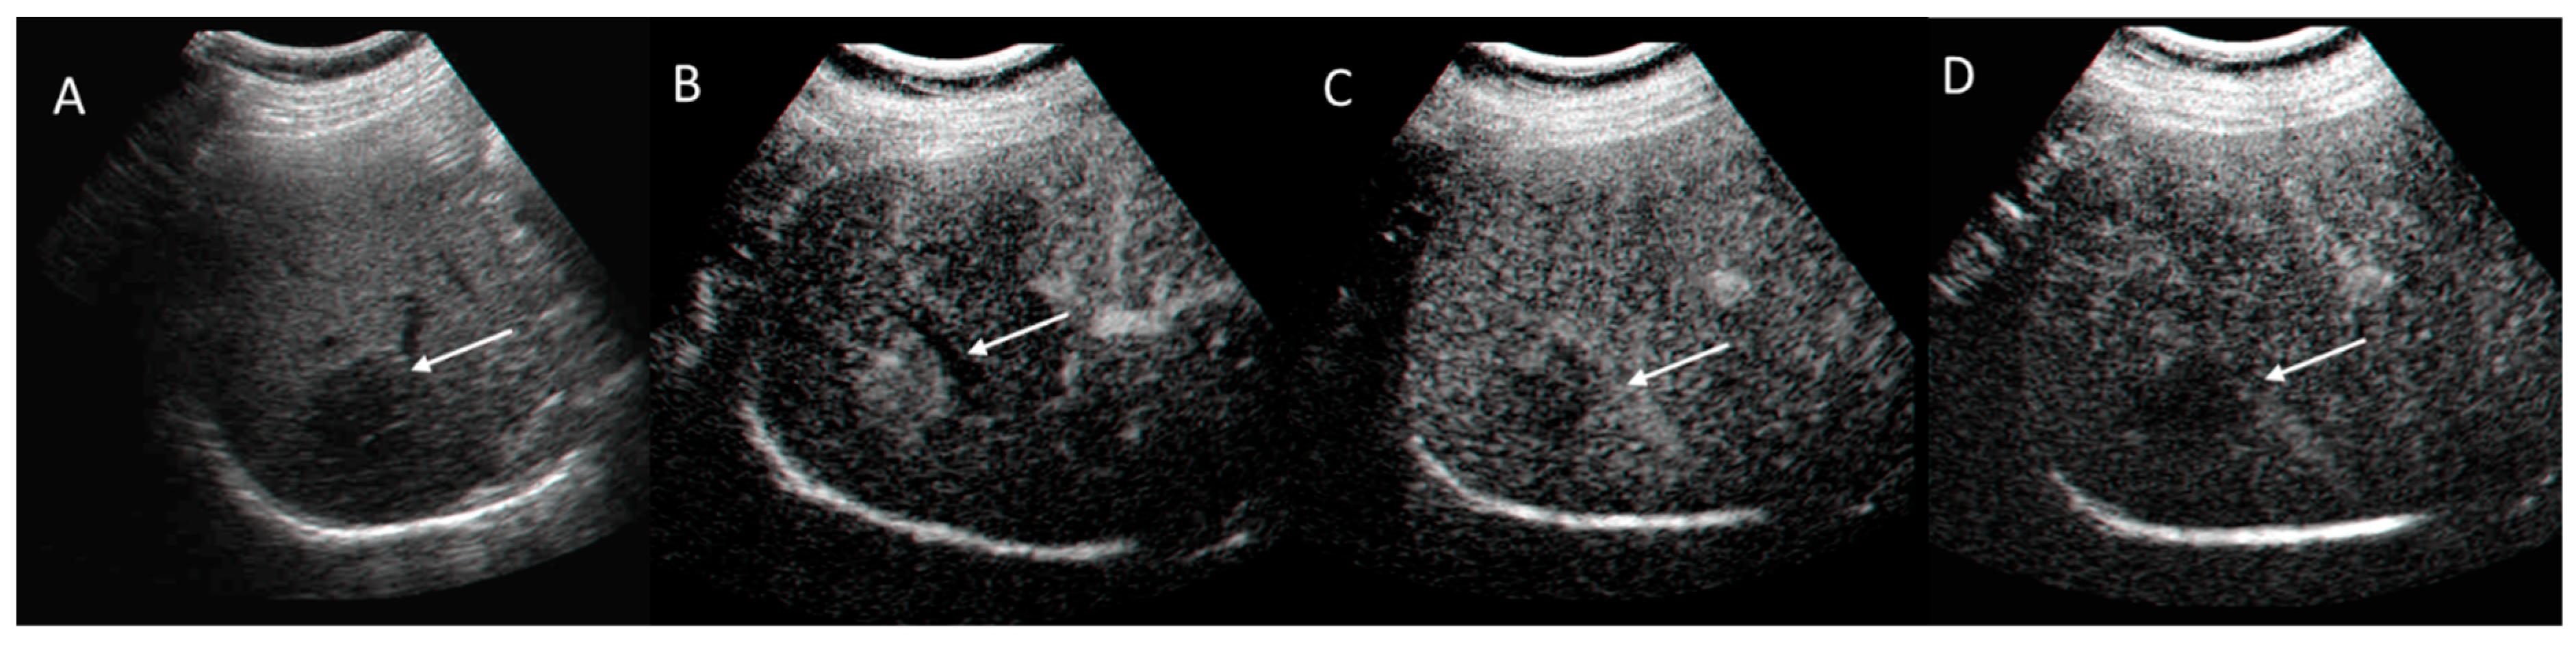

2.3. CEUS-LI-RADS

2.3.2. CEUS-LI-RADS Categories

2.3.3. CEUS-LI-RADS vs. CT/MRI LI-RADS